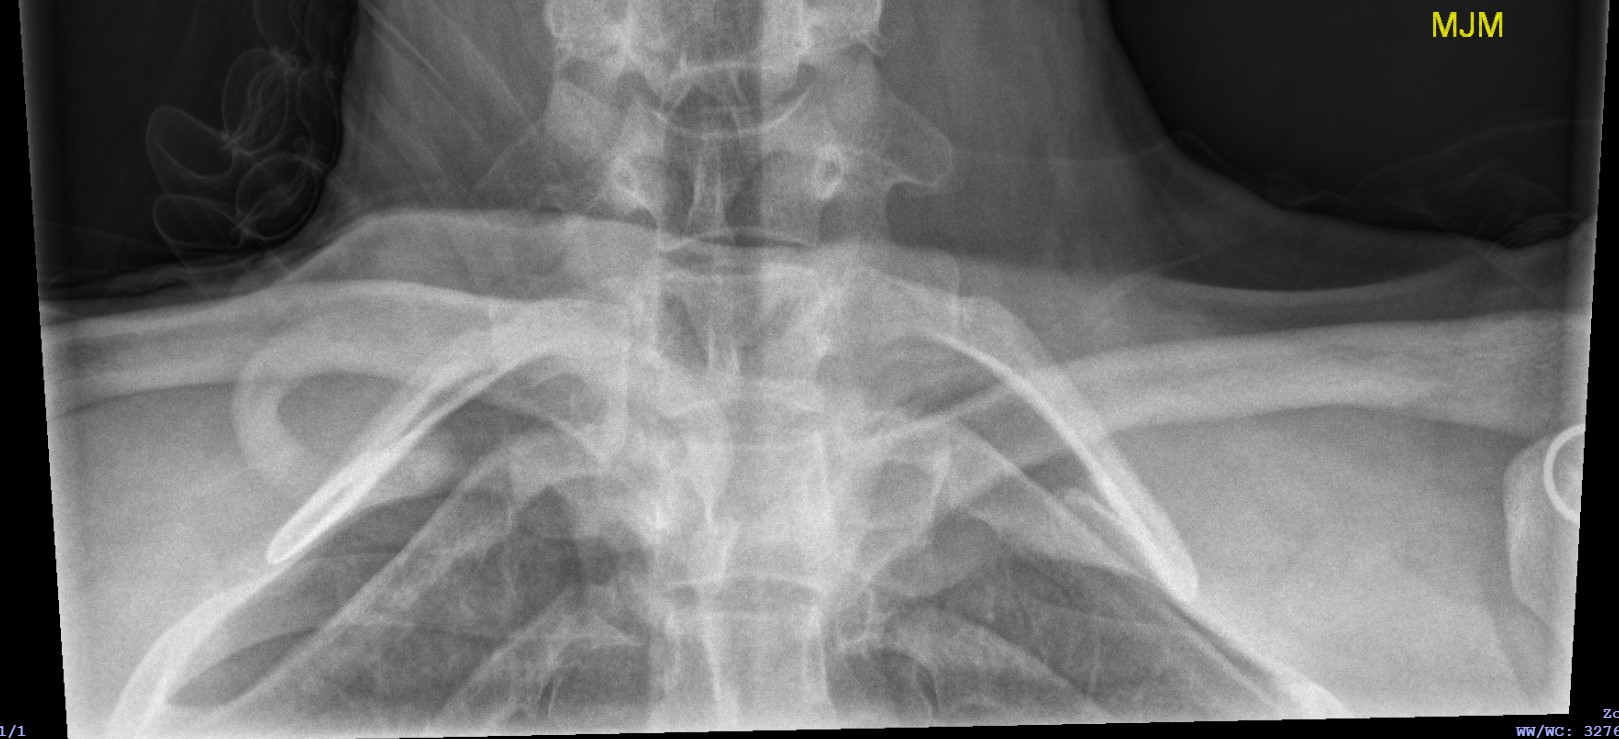

Xray

Can be missed on a xray

Left posterior SCJ dislocation with pre- and post angiogram

Severe left posterior SCJ dislocation with subclavian vein compression